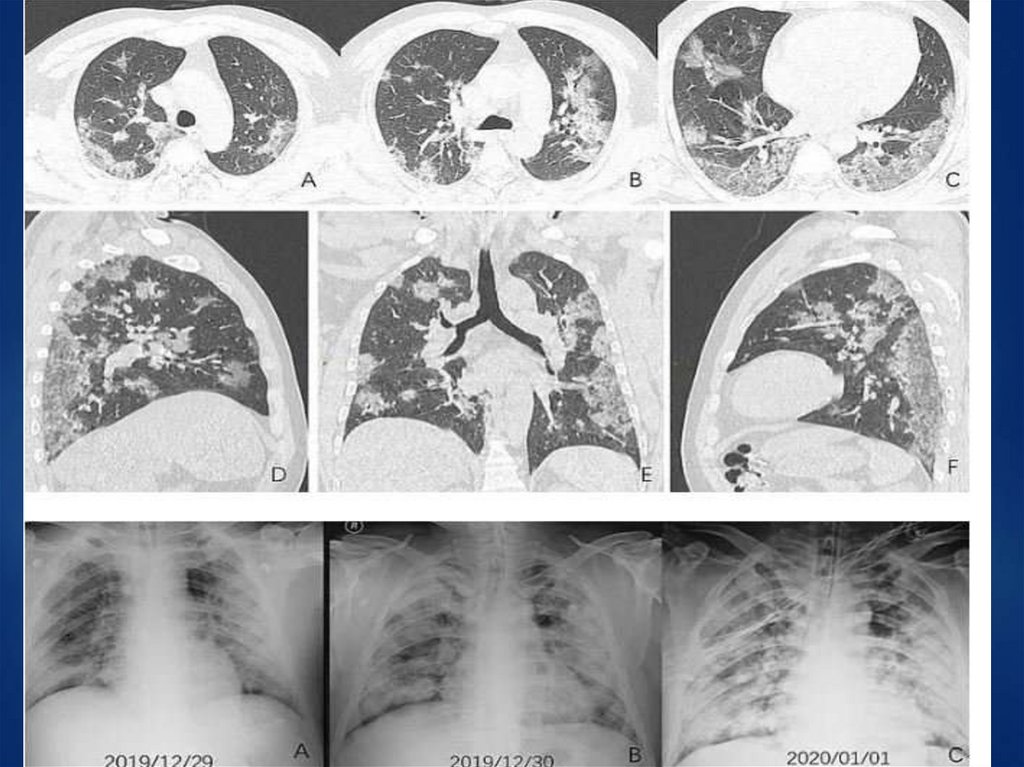

МТС рака щитовидной железы